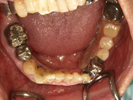

50代女性

![]() |

治療前 |

||

治療中。仮歯。 左上の奥にインプラント埋入。 噛みあわせ治療を行いました |

治療後 全体の歯で食事がおいしくできるようになったと喜んでおられました。 |